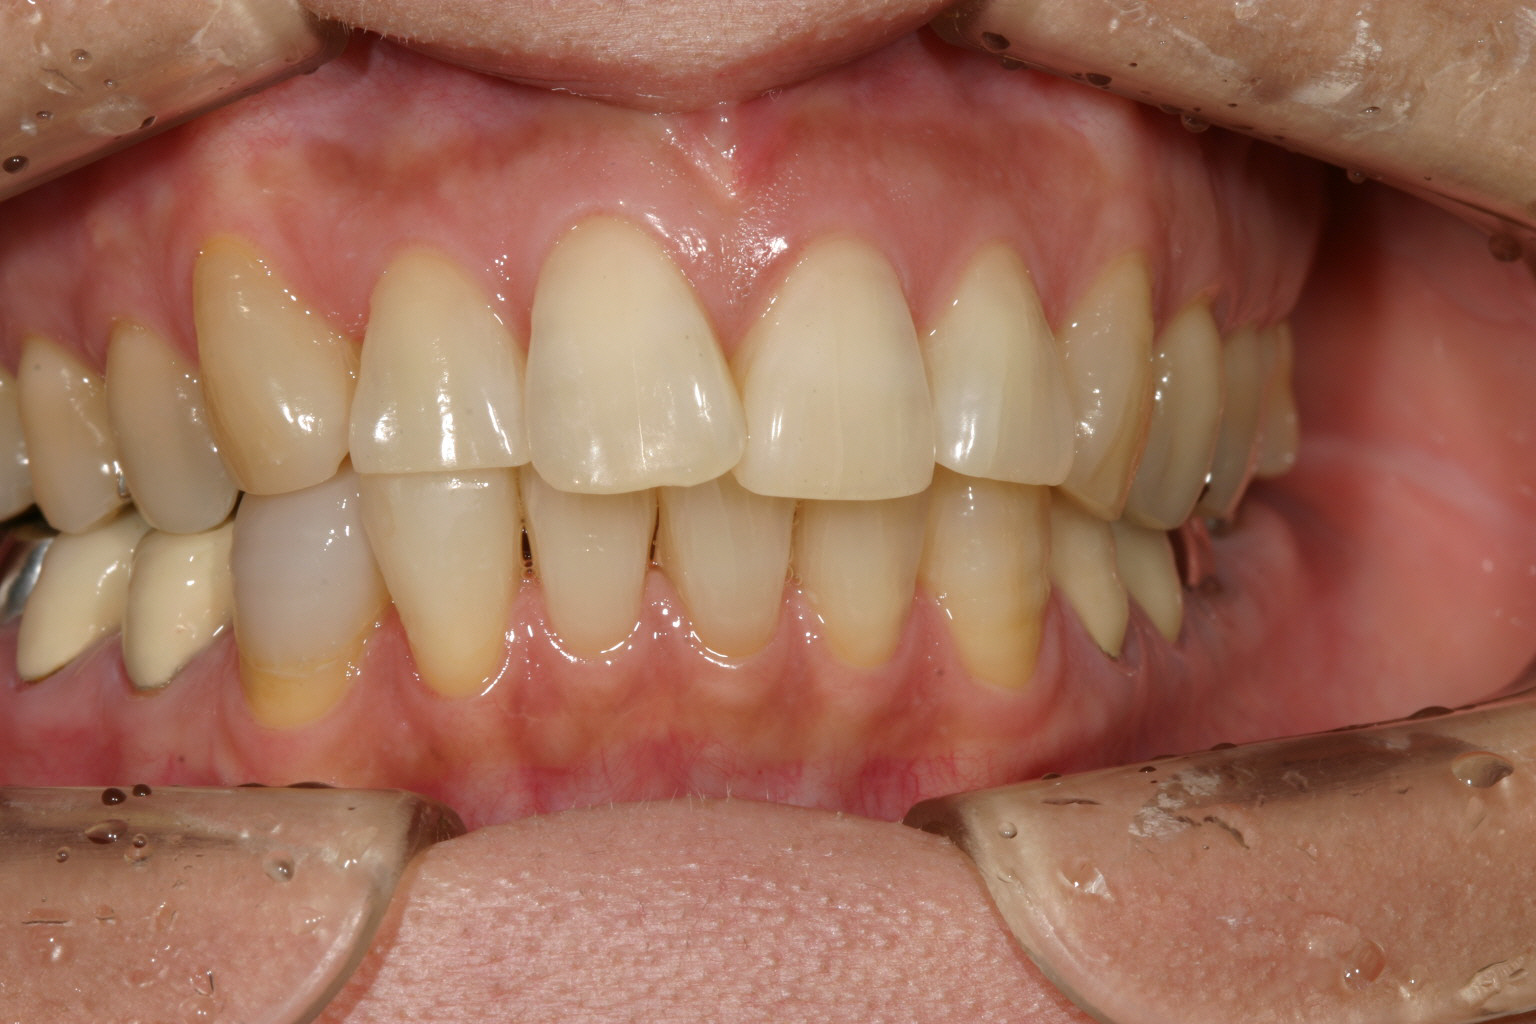

上顎にはさほど乱れを認められません。

多少の過度なオーバージェットが認められます。

綺麗に咬合してます。 最初の正面観見て頂ければ正中が左にシフトし改善しているのが分かります。